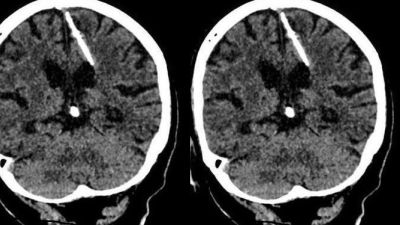

اكتشف اطباء روس بالصدفة ابرة طولها ثلاثة سنتمترات موجودة منذ ثمانين عاما داخل دماغ امرأة مسنة اثناء قيامهم باجراء فحص لها بالتصوير المقطعي.

وأضافت أن الفحوص اظهرت ان المراة تعيش مع الابرة البالغ طولها ثلاثة سنتمترات داخل دماغها "منذ ولادتها" ما يؤكد ان والديها كانا قررا التخلص منها، لكن محاولتهما لم تفلح.

واوضحت الادارة ان الفحص اظهر ان الابرة اخترقت الفص الجداري الأيسر لدماغ المراة، لكنها كتبت لها النجاة حيث لم يتسبب ذلك في وفاتها كما كان يأمل والداها.